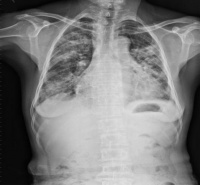

(2)内脏器官感染 如肺炎脓胸中耳炎脑膜炎心包炎心内膜炎等,主要由金葡菌引起。